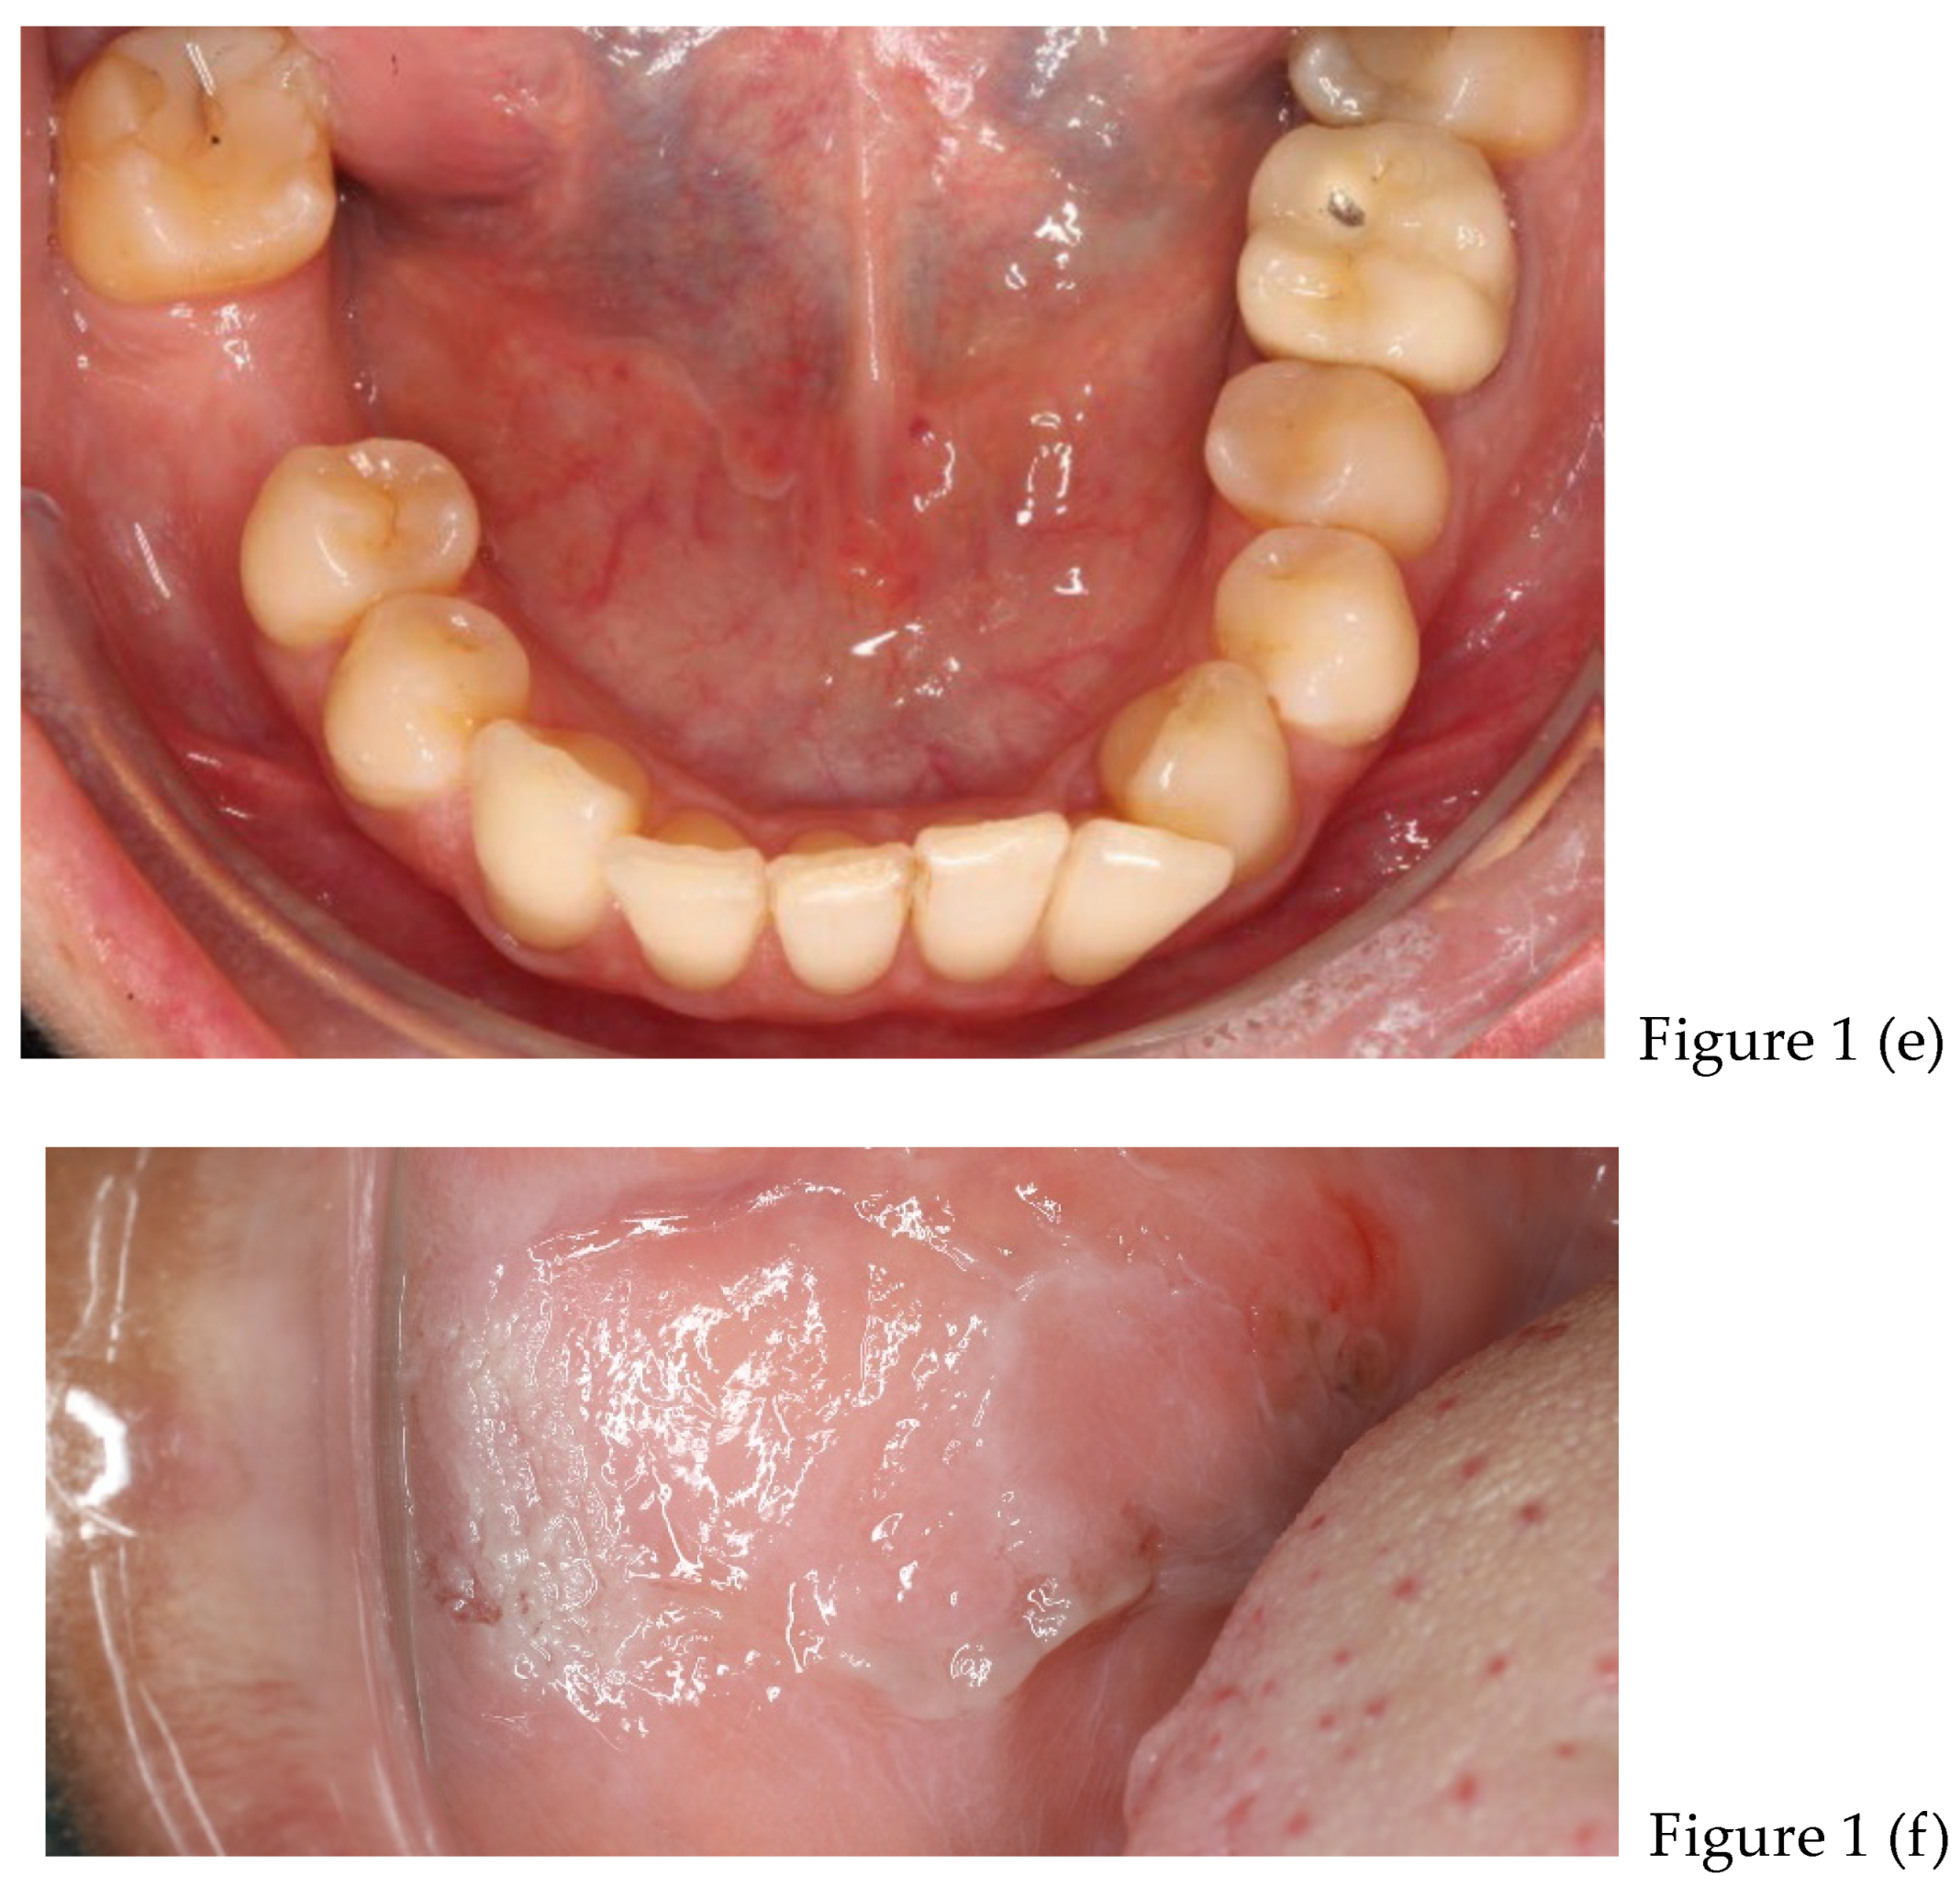

| preliminary photos | |

| after 8 months | Retainers + CBCT (t1) + final photos |